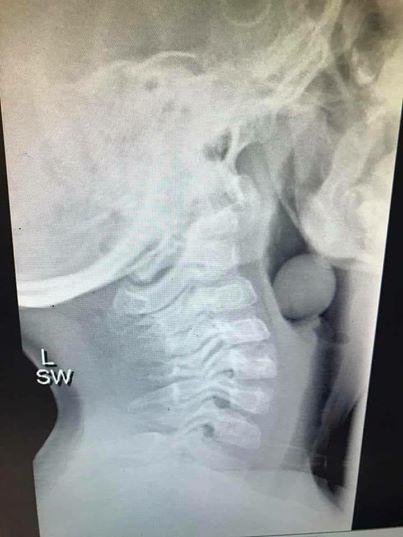

Mới đây, cô Angela Henderson là bác sĩ người Australia, blogger và cũng là một bà mẹ đã chia sẻ bức ảnh chụp X-quang cổ họng của một bệnh nhi 5 tuổi khiến các bậc phụ huynh phải đặc biệt quan tâm.

Bức ảnh cho thấy cổ họng của bé trai đã bị một vật gì đó chặn lại và mắc kẹt bên trong. Angela viết: “Bạn có biết cái gì trong bức ảnh chụp X-quang này không? Đó là một quả nho. Một quả nho đã chặn ngay họng của một đứa trẻ 5 tuổi. Cậu bé đã được phẫu thuật để loại bỏ vật cản ra. May mắn khi một phần đường thở của cậu bé không bị chặn nên đã không có kết cục tồi tệ nào xảy ra.”

Hình ảnh phim chụp X-quang cổ họng của bé trai bị một quả nho chặn.